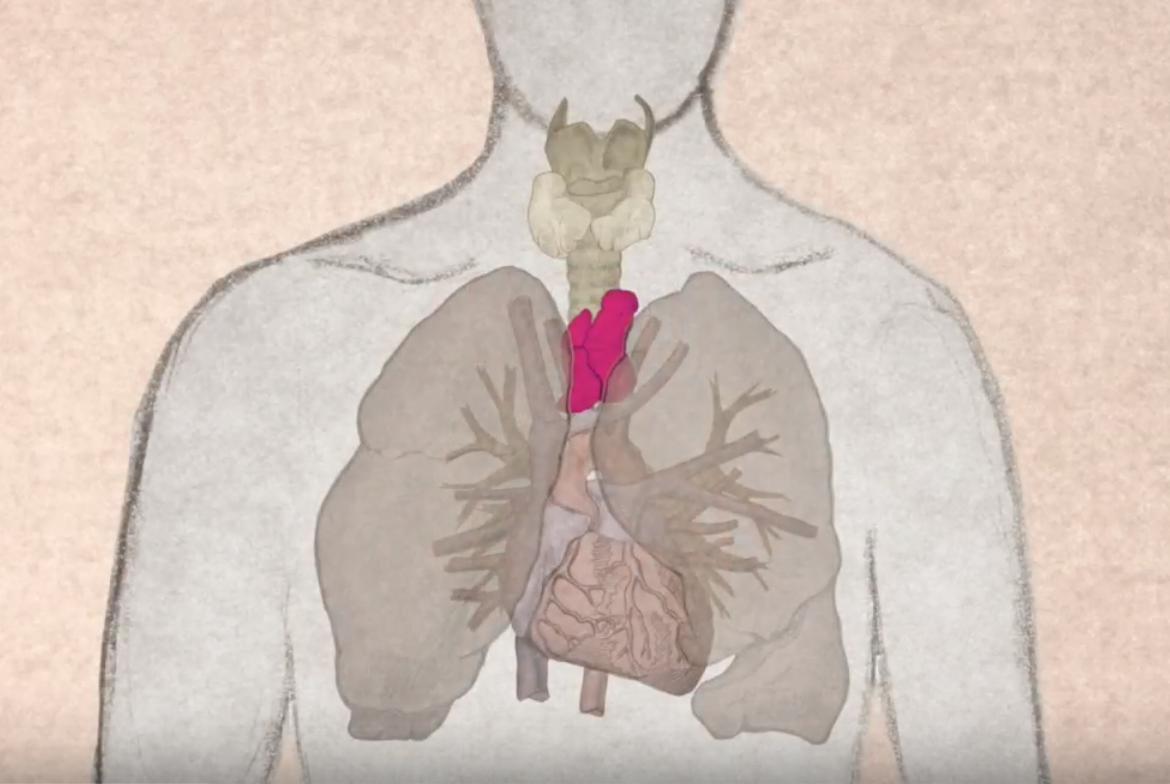

Фотографии вилочковой железы тимуса: структура и функции

Раздел: Снимки-откровения